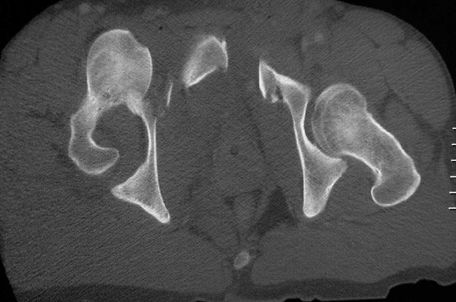

髋关节后脱位

髋关节前脱位

先天性髋脱位

常见髋关节测定线